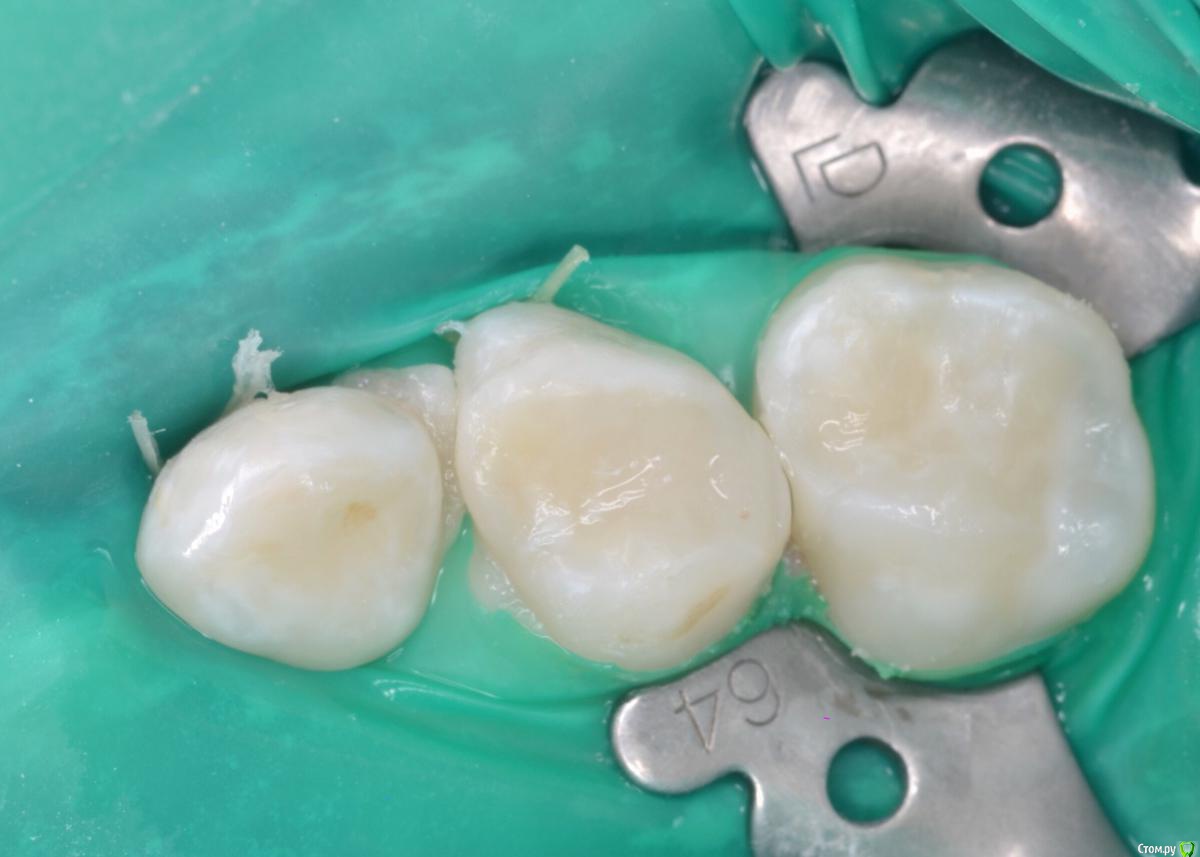

CRAZYDUCK Опубликовано 20 мая, 2018 Автор Поделиться Опубликовано 20 мая, 2018 Вовремя замеченный кариес не успеет превратиться в пульпит . Поверхностный кариес контактных поверхностей 6.5 и 6.4 зубов, подтверждённый RVG исследованием . Серёже 3,5 года , но он большой молодец , продолжительность 45 минут ( анестезия, коффердам , преп турбиной и рондофлекс , пломбирование и полировка. 1 Ссылка на комментарий